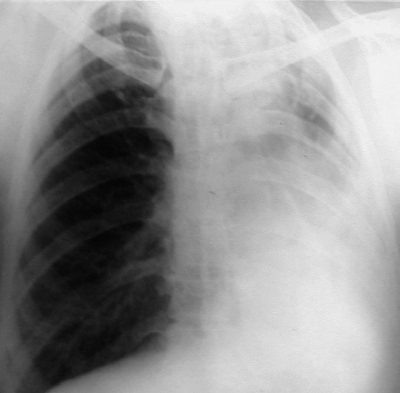

При выраженной форме туберкулёза ВГЛУ аденопатию можно обнаружить при обычном рентгенологическом исследовании (рис. 18-8). На рентгенограмме в прямой проекции воспаление узлов бронхопульмональной и трахеобронхиальной групп в ранней фазе проявляется увеличением тени корня лёгкого в длину и ширину. Наружная граница корня становится выпуклой и размытой, нарушается его структура, невозможно различить бронхиальный ствол. При поражении паратрахеальных лимфатических узлов наблюдают расширение срединной тени с полукруглым или полициклическим краем. При рассасывании перинодулярных воспалительных изменений и плотной консистенции лимфатические узлы визуализируются лучше и имеют чёткие контуры. В таких случаях изменения, выявляемые при рентгенологическом исследовании, сходны с картиной опухолевого поражения (рис. 18-9).

Рис. 18-8. Туберкулёз ВГЛУ (бронхопульмональная группа) слева. Обзорная прямая рентгенограмма.